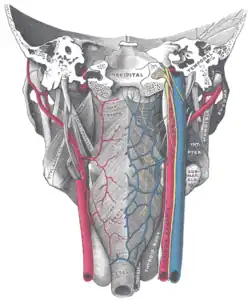

Músculos da faringe, visto por trás, juntamente com os vasos e nervos associados.

Músculos da faringe, visto por trás, juntamente com os vasos e nervos associados.